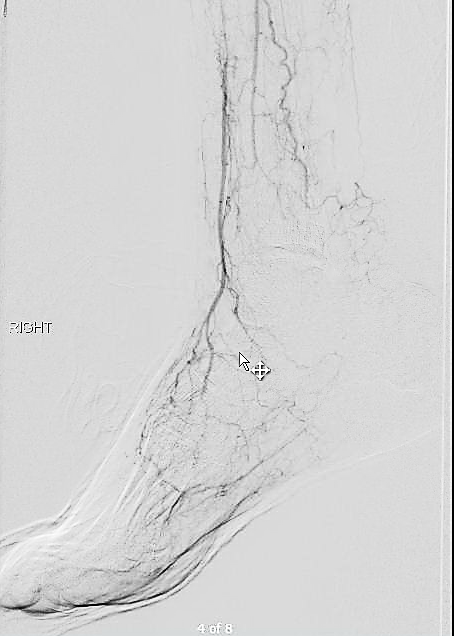

At followup several months after the procedure, the patient was walking well without claudicating and was ready to return to work. PVRs showed excellent flows down to the toes.